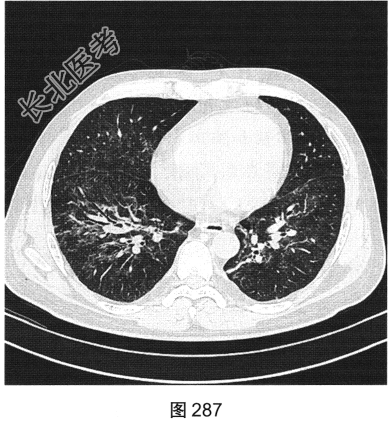

- [材料题] 患者男性,33岁,因“双下肢散在皮下出血点伴尿检异常3个月余,咳嗽、胸闷伴发热一周”就诊。患者脂肪肝、胆囊炎,服用莲葡双清片;随后几日内食用淡水鱼、鱿鱼、饮啤酒;5天后出现双下肢散在皮下出血点,未重视;10天后出现腹痛,在当地医院检查尿中有蛋白、定量不详,血常规检查正常,肾功能正常,应用醋酸泼尼松效果欠佳,行肾活检术,病理诊断:紫癜性肾炎,继发IgA肾病。患者每天静脉滴注甲泼尼龙0.5g,共3天,后改为口服甲泼尼龙28mg/d,共35天。一周前着凉后出现咳嗽、胸闷伴发热,体温达39.1℃,于当地医院抗炎治疗效果欠佳,遂来本院。实验室检查:血白细胞计数6.92×109/L,中性粒细胞0.845,CRP为2.7mg/dl。患者PP65阳性。胸部CT检查如图284~图287所示。

- 多项选择题4.该病的常见影像表现有( )

A、空洞

B、双肺磨玻璃影

C、淋巴结增大

D、实变

E、小叶中央结节一树芽征

F、血管支气管束和小叶间隔增厚